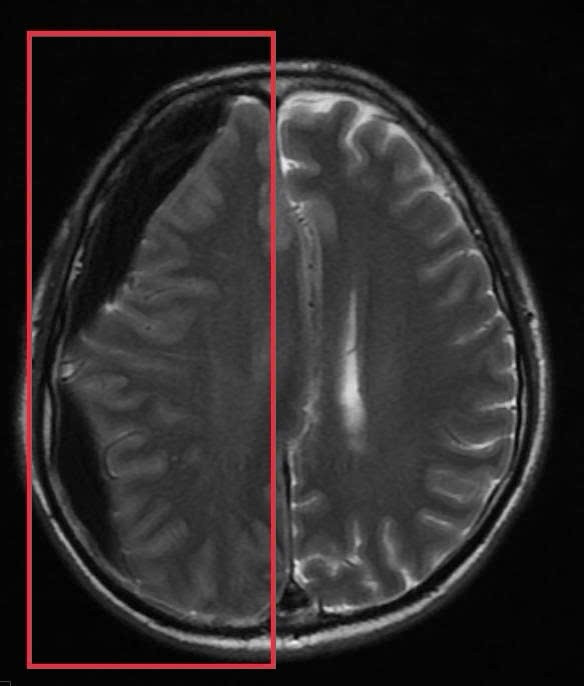

Hình ảnh tụ máu não dưới màng cứng khi nhập viện, trước phẫu thuật - Ảnh BVCC

Trước băn khoăn của gia đình, BS Huyền đã tư vấn ưu tiên chụp MRI sọ não. Kết quả chụp MRI sọ não cấp đã xác định người bệnh có khối tụ máu não dưới màng cứng mạn tính kích thước lớn vùng thái dương, gây hiệu ứng khối và đè đẩy đường giữa của não.

Đây là tình trạng đặc biệt nguy hiểm, bởi khối tụ máu có thể tiến triển âm thầm trong nhiều tuần với triệu chứng kín đáo như chậm chạp, giảm trí nhớ, rối loạn ngôn ngữ nhưng có nguy cơ cao dẫn đến liệt vận động, tụt kẹt não, hôn mê và tử vong nếu không được xử trí kịp thời.

Ngay sau khi có kết quả chẩn đoán hình ảnh, ông P.V.D được chuyển sang chuyên Khoa Phẫu thuật thần kinh sọ não để phẫu thuật cấp cứu lấy bỏ tụ máu, giải phóng chèn ép nhu mô não. Đồng thời, người bệnh được chỉ định điều trị thuốc kháng động kinh do đã có nhiều cơn co giật rõ ràng trước đó. Sau can thiệp, tình trạng ý thức cải thiện tốt, không xuất hiện cơn co giật.